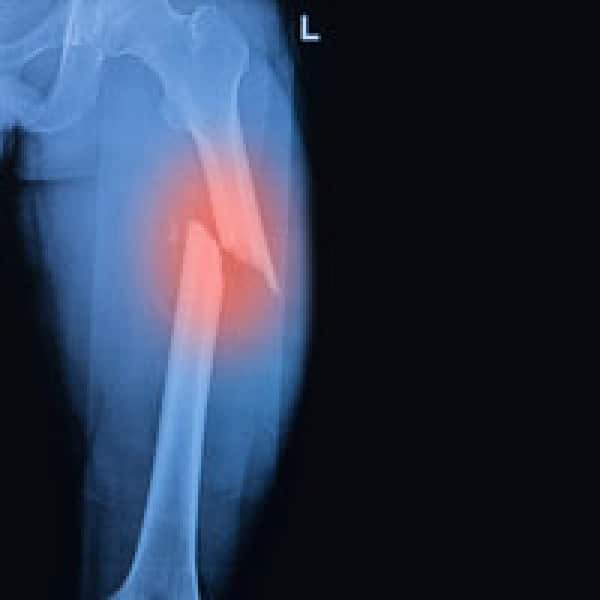

More Scientific Proof That Bisphosphonates Destroy Bone And Cause Atypical Fractures

bisphophonates broken femur

Alert! Never-Published Study Uncovers How And Why Bisphosphonates Cause Atypical Fractures